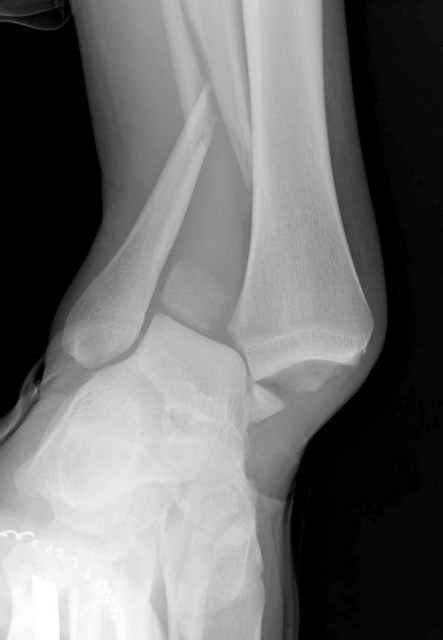

Неравномерность суставной щели может быть связана с разрывом глубокой порции дельтовидной связки и ротацией м/берцовой кости за счет поврежденных структур синдесмоза(репозиция ее на уровне перелома как-будто удовлетворительная).

По моему мнению,ассиметрия суставной щели обусловлена импрессией медиальной части суставной поверхности б/б кости. Да, позиционный винт здесь не лишен, но через 4 недели целесообразность его проведения сомнительна, брейс, ограничение осевой нагрузки достаточно.Есть еще деонтологические аспекты повторной операции, не все так плохо выполнено предыдущим доктором!

Импрессия медиальной части суставной поверхности бывает при супинационном механизме перелома лодыжек (тип А по классификации АО). Здесь механизм пронациия+наружная ротация (тип С, синдесмоз и межкостная мебрана повреждены),

перелом медиальной лодыжки отрывной, при этом в 20-30% бывает повреждение дельтовидной связки.

Мое мнение, что никакой ротации малоберцовой кости здесь нет и синдесмоз тоже впорядке. Все дело в некачественно репозиции медиального мыщелка. Скорее всего его или немного ротировали при операции или сместили латерально. Более склонен ко второму варианту.

Присоединяюсь к ранее высказанным мнениям о необходимости вмешательства.

Перелом типа Вебер С с эверсионным механизмом травмы всегда сопровождается повреждением дистального межберцового синдезмоза, поэтому вместе с фиксацией переломов лодыжек( малоберцовой кости) автоматом выполняется фиксация синдесмоза винтом, который обычно удаляется через 8 недель -

перед началом полной нагрузки на ногу.

Конечно, компьютерный томограф более информативный метод, но с помощью недорогого обычного стандартного в нейтральном положении стопы: прямого, бокового и косой (ankle mortise) ренгенологического метода можно получить полную информацию о повреждении голеностопного сустава, а сравнительный снимок с другой стороны подтвердить наличие повреждения.

Расширенная медиальная щель более чем на 4 мм и укорочение малоберцовой более чем 2 мм, а перелом заднего края большеберцовой смещения более 2мм с вовлечением 30% поверхности сустава, считается отходом от нормы голеностопного сустава, и подлежит к оперативному вмещательству.